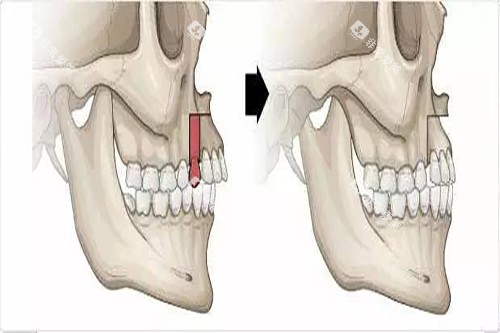

二、牙齿矫正项目

项目名称 | 价格(元) |

传统金属托槽矫正 | 5900起 |

金属自锁托槽矫正 | 18000起 |

陶瓷托槽矫正 | 20000起 |

隐形矫正 | 17000起 |

说明:牙齿矫正项目提供多种选择,从传统的金属托槽矫正到隐形矫正,满足不同年龄段和需求的患者。隐形矫正技术如隐适美和时代天使,不仅美观,还方便患者日常生活。